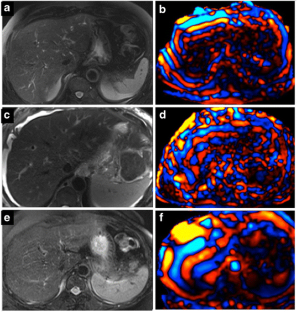

Fig. 1

Fig. 2

Fig. 3